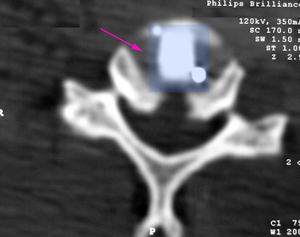

Πρόσθια αυχενική δισκεκτομή και σπονδυλοδεσία με κλωβό από PEEK (μπλέ) Α5-Α6. |

Πρόσθια αυχενική δισκεκτομή και σπονδυλοδεσία με κλωβό από PEEK (μπλέ). |